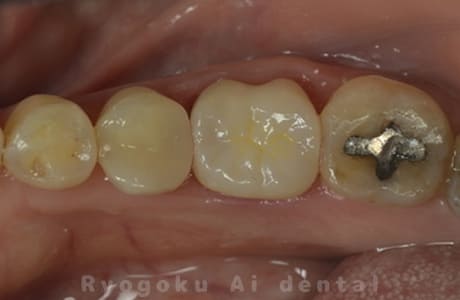

Case10

-

- 原因

- 右上6番パーフォレーション

- 治療内容

- マイクロエンド治療(パーフォレーションリペア)、ゴールドクラウン修復

- 治療費用

- 297,000円

右上奥歯を他院で抜歯と言われ、残して欲しいとのことでご来院された患者様です。穴が空いている部分をMTAでリペアを行い、再度マイクロスコープ下で根管治療を行い、ゴールドクラウンで修復しました。経過も良好で、大変満足して頂けました。

<リスク・副作用>

術後は痛み、腫れ、痺れなどの副作用が生じる場合があります。症状が再発する可能性があります。